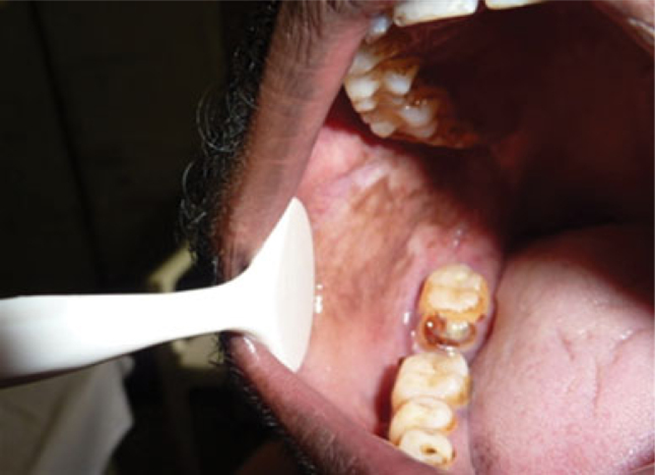

Nine patients (21%) were found to have cranial nerve impairment. Five patients (12%) were found to have involvement of the trigeminal nerve and four patients (9%) had involvement of the seventh cranial nerve. Twenty-one patients (49%) had extra-oral lesions which included nodules, erythema and hypopigmented patches of anaesthesia (Figures 1 and 2). Twelve patients (28%) had intra-oral lesions which included sinuses and diffuse areas of hyperpigmentation (Figures 3 and 4). Out of these 12 patients, nine (21%) also chewed either paan, or tobacco or both. Only one patient had intra-oral ulceration and this was in the gingivae above the upper left central the patients examined exhibited any bony or skeletal changes. Figure 1

Figure 3: Open in a new tab Hyperpigmented intra-oral lesions on the buccal mucosa and palate.

Figure 4: Hyperpigmented intra-oral lesions on the buccal mucosa and palate.